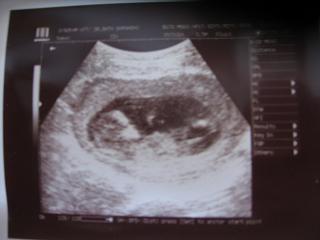

Hát ja és sem értem a méricskéléseket, de tegnap végül megbeszéltük a saját dokimmal, h. már 12 hetes és 2 napos és igaz a CRL-t megint nem tudom

Szóval, tegnap én a ballagásról estem be a dokihoz, de végül nem késtem! Minden okés, nagyságát nem tudom

Ballagás is és a uh is nagyon megható volt!